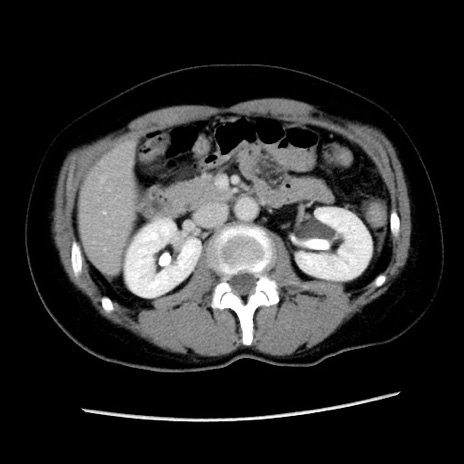

冠状断像

矢状断像